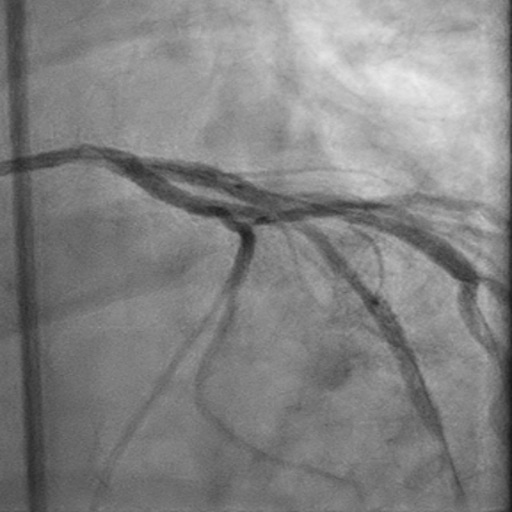

Left Anterior Descending CTO PCI

Dual injection (right radial and right femoral). EBU 3.75 6 Fr. Finecross Microcatether. Unsuccessful crossing attempts with Sion Blue and Whisper wires and final successful crossing with Gaia III, then exchanged for a BMW wire. Predilation with 1.5 x 15 mm and 2.5 x 15 mm semi-compliant balloons. PCI of left anterior descending-first diagonal bifurcation with stepwise provisional approach. Implantation of two Xience DES (2.75x23 mm and 3x28 mm, distal to proximal, respectively, overlapping), followed by POT-Kiss-POT. Optimal TIMI flow at completion.